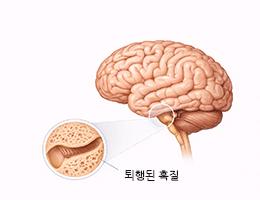

치매 (Dementia)

파킨슨병 (Parkinson’s Disease)

뇌졸중 (Stroke)

뇌출혈 (ntracerebral Hemorrhage)